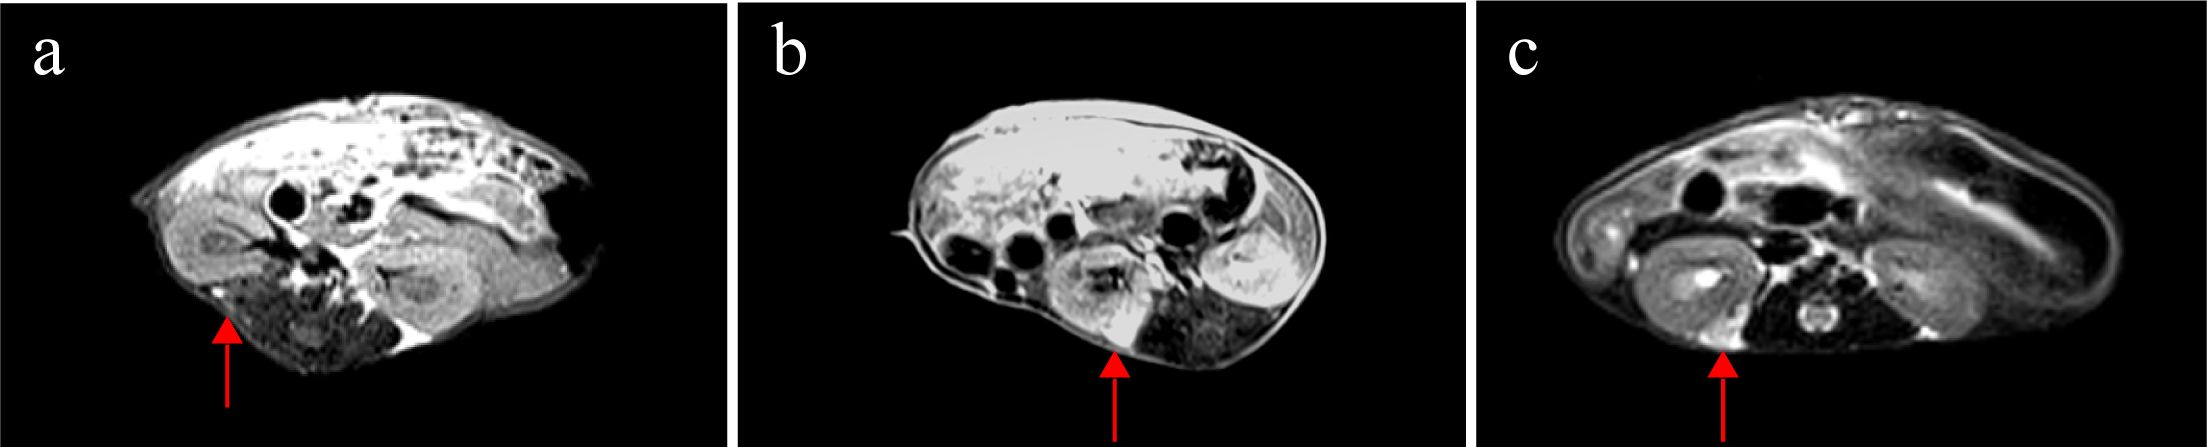

Weekly MRI observations were performed on the PDX. The tumor’s long and short diameters were measured using the software’s measurement tools. Serial observation of a PDX model revealed tumor growth dynamics, with measured long diameters of 2.5 mm, 2.1 mm, 2.0 mm, and 2.7 mm on days 8, 16, 25, and 32, respectively (Figure 2). The PDX tumor showed, Isointense and Hypointense on T1WI (Figure 3a), obvious Marked enhancement on T1WI contrast-enhanced(T1WI+C) scans (Figure 3b), Isointense and Hyperintense signal on T2WI (Figure 3c), companying with renal compression. When the tumor volume reached 100–500 mm³, the T2WI sequence was used to measure and calculate the tumor volume in the coronal (Figure 4a) and transverse (Figure 4b) planes. Subsequently, the mice were euthanized, and the tumors were excised (Figure 4c), Histopathological analysis diagnosed gastric adenocarcinoma (Figure 4d). The length and width of the tumors were measured using a vernier caliper, and the tumor volume was calculated. A comparison with the last MRI results showed no statistically significant difference between MRI and vernier caliper measurements of tumor volume: [(279.91 ± 78.94) vs. (277.10 ± 78.79), t = 1.41, P = 0.171] (Figure 4e).

Figure 4

Comparison between MRI and vernier caliper (VC) measurements: Pre-excision MRI: T2WI sequences were performed (a) coronal plane; (b) transverse plane. Post-excision: (c) the PDX tumor was extracted. (d) histopathological analysis verified the tumor as gastric adenocarcinoma. (e) no significant difference was observed between tumor volumes calculated from MRI and VC measurements (ns, P > 0.05. n=28).

In PDX models, caliper measurements can be used to determine tumor size; however, this method proves challenging for gastric cancer PDX models in the renal capsule, typically requiring serial necropsies. Previous studies have found that among FDG-PET/CT, contrast-enhanced MRI and non-contrast MRI, non-contrast T2w MRI was the most effective and efficient imaging technique (32). Similarly, our study compared T2WI sequences with contrast-enhanced T1WI (T1WI+C) and found both modalities could clearly visualize renal capsule PDX. Notably, T2WI eliminated the need for contrast agent injection, thereby reducing examination time and avoiding potential trauma to mice from contrast administration. In this study, renal capsule PDX was first detected as early as day 8. On imaging, the PDX exhibited Hyperintense on T2WI and Hypointense intensity on T1WI compared to adjacent muscle tissue, with post-contrast marked enhancement indicating vascularization. These findings demonstrate MRI’s capability for early PDX detection. Consistent with prior research (33), our measurements from T2WI sequences showed no significant difference from caliper measurements, with pathological confirmation of gastric cancer PDX. Previous studies have demonstrated that PDX tumors maintain consistent histological characteristics compared to their original primary tumors (34–37). Our findings align with this observation, as the PDX models from F0 to F3 generations preserved the histological features of poorly differentiated adenocarcinoma. Notably, the number of Ki67-positive cells - reflecting cellular proliferative activity (38) - showed no significant differences across the F0-F3 generations.